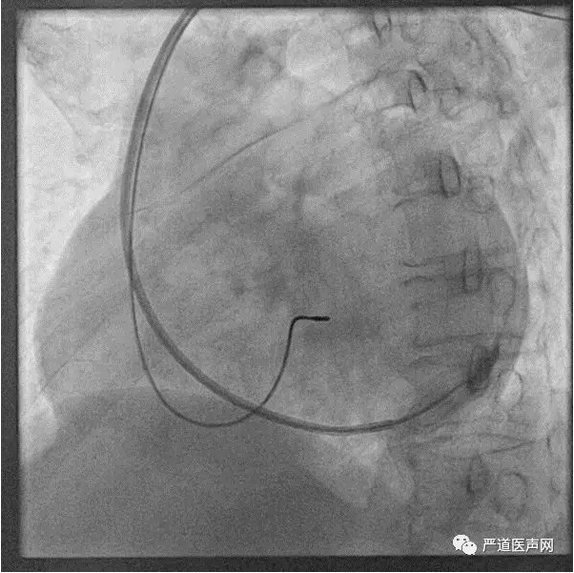

寻找CS开口方案三:特殊塑形左室递送鞘

● 不同弯度的鞘管应对各种患者的解剖变异,用于直接寻找CS

● 右侧植入推荐使用直鞘或右侧专用鞘

外径9F,内径7.2F

右侧鞘(6250MPR)

● 将左室长鞘插入冠状静脉时须特别小心

● 因为鞘管相对较硬,一旦损伤血管壁时会引起夹层或穿孔

● 建议配合EP电极、导引钢丝